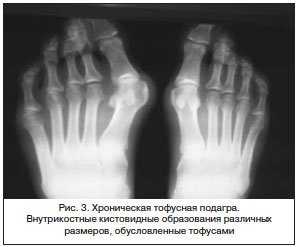

Для подагры типичны внутрикостные кистовидные образования различных размеров, обусловленные тофусами, которые могут располагаться внутри сустава, но, что особенно примечательно, рядом с ним и даже на некотором отдалении. Хронический подагрический артрит может сопровождаться деструкцией хряща (сужение щели сустава) и развитием краевых костных эрозий. Так называемый «симптом пробойника» – краевые костные эрозии или кистовидные образования правильной формы с четкими, иногда склерозированными контурами – наблюдается при подагре нечасто и для нее неспецифичен. Для этого заболевания более характерна возникающая с течением времени выраженная деструкция не только субхондрального участка кости, но и всего эпифиза и даже части диафиза (внутрисуставной остеолиз). При этом могут наблюдаться значительное расширение «изъеденных» суставных отделов костей и заострение их краев. Костные анкилозы при подагре описаны, но наблюдаются чрезвычайно редко (рис. 3).

Всегда своеобразна при подагре локализация рентгенологических изменений. Обычно наиболее выраженная патология обнаруживается в суставах стоп (в первую очередь в суставах больших пальцев) и кистей. Редкой, но известной локализацией рентгенологических изменений при подагре являются плечевые, тазобедренные, крестцово-подвздошные суставы и позвоночник. Важно отметить, что деструктивные изменения суставов или внутрикостные кисты рассматриваются как признак «тофусной» подагры.